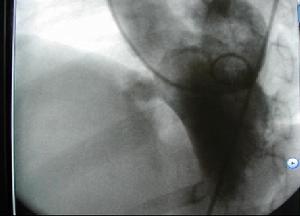

6.如需持續引流,可經軟性J字形導絲引入擴張管,然後插入多孔豬尾巴導管(導絲位置應通過兩個投射位透視確認),待心包引流液小於25ml/d時拔除導管。

8.對心包積液量較少(200~300ml或<200ml)者使用切線進路側位透視觀察心外膜暈輪現象可增加穿刺成功率並減少併發症。